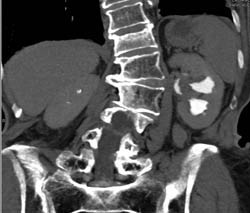

Post- Radiofrequency Ablation (RFA) Changes in Left Kidney